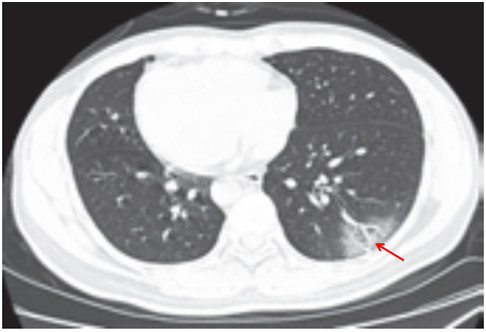

(五)结节伴晕征

部分案例实性结节病灶周围出现磨玻璃密度影,边缘模糊,称为晕征

根据既往病理学机制提示,病灶中心实变影为肺泡腔内聚集大量富细胞渗出液,显示为实性密度灶;其周围肺泡亦见渗出,包含炎症细胞、蛋白质、纤维素等,形成“膜状物”,或形成磨玻璃密度阴影(图 2-5)

图 2-5 结节伴晕征(A和B)